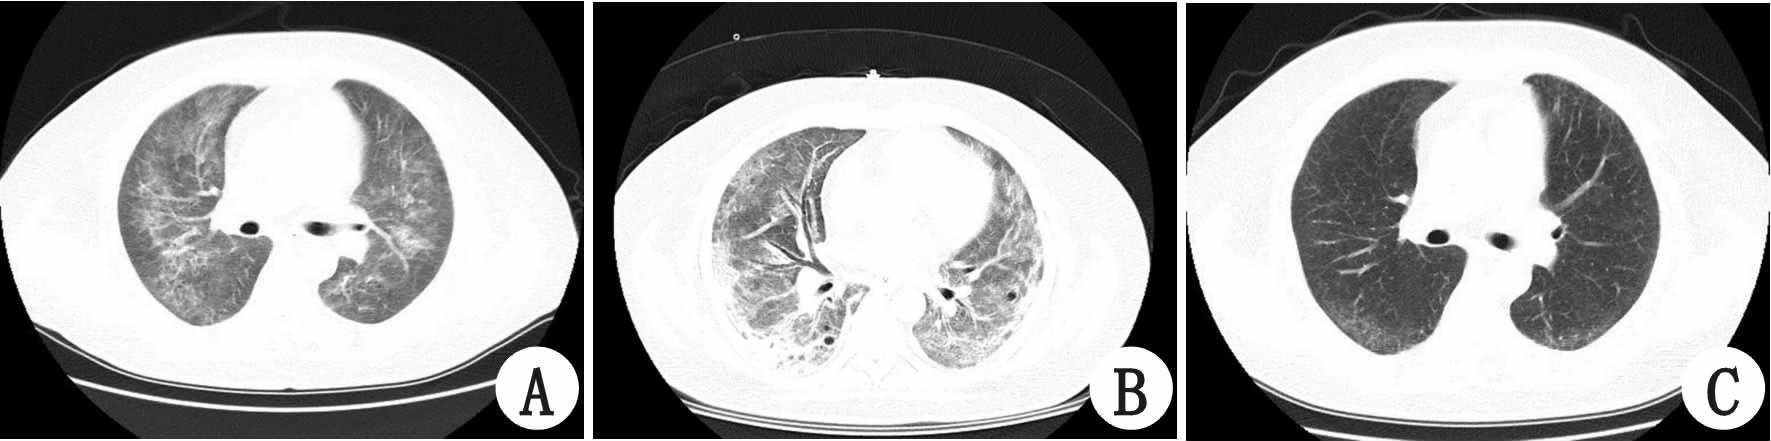

1 资料与方法患者,男性,45岁,既往体健,因“皮肤出血点2个月”于2015年9月22日收入大连医科大学附属第一医院血液科。曾就诊于当地医院,血红蛋白及血小板呈进行性下降,骨穿后诊断为骨髓增生异常综合征-难治性血细胞减少伴多系发育异常,疗效差。间断头痛难忍,双手麻木,发作性言语不清,且神经系统症状进行性加重,出现黄疸。查体:T 36.9 ℃,P 72次/min,R 18次/min,BP 110/70 mmHg(1 mmHg=0.133 kPa);贫血貌,全身散在出血点,巩膜及皮肤黄染;心肺腹及神经系统未见阳性体征。我院头部CT未见异常;血白细胞6.82×109/L,血红蛋白68 g/L,血小板11×109/L;总胆红素39.4 μmol/L;乳酸脱氢酶1 121 U/L;网织红细胞比例16.69%;外周血涂片破碎红细胞>10%;ADAMTS13活性<2.5%(正常值68%~131%);尿蛋白质++,尿潜血阳性;肌酐正常;Coombs试验(-),我院诊断为TTP。因病情恶化,出现神志不清,呼吸困难,2015年9月29日转入急诊ICU行机械通气;右股静脉穿刺成功后予血浆置换,3 000 mL/d,静脉滴注甲强龙160 mg/d。10月3日血小板升至131.4×109/L,血浆置换量减为2 000 mL/d;10月5日血小板骤降至9.4×109/L,穿刺处渗血,右下肢肿胀且大面积淤青,予局部有效压迫止血,血浆置换量再增至3 000 mL/d,出血倾向好转,10月6日神志转清,10月8日撤呼吸机。然而,在此期间血小板仍低 ,遂将血浆置换量增至3 500 mL/d,并加用利妥昔单抗600 mg/次,每周一次,10月16日血小板升至101×109/L,未再下降,血浆置换量渐减至2 000 mL/d。10月28日复查ADAMTS13活性64%,11月1日出院。共行血浆置换27次,总量达74 500 mL。出院后继续口服泼尼松片,定期复查血小板均正常。该患者12月11日起出现发热,体温39 ℃,咳嗽、少痰,入住外院查血常规正常,PCT 0.134 ng/mL,给予头孢唑林静脉滴注,12月16日肺部CT(图 1A)提示双肺弥漫毛玻璃样斑片影,考虑真菌性肺炎可能,换用卡泊芬净联合莫西沙星后疗效较差,出现喘憋,SPO2降至65%。12月18日转入我科行机械通气,复查肺CT(图 1B)示双肺弥漫性毛玻璃密度影,双肺间质纤维化或间质性肺炎,较前加重;痰真菌培养回报为阴性,细菌培养为正常咽喉菌群生长;G实验291.3 pg/mL,GM实验阴性。经呼吸内科会诊考虑为肺孢子菌肺炎,继续用卡泊芬净联合莫西沙星,加复方磺胺甲噁唑口服,症状渐好转,成功撤呼吸机出院。继续口服复方磺胺甲噁唑,1月22日复查CT见图 1C病灶基本吸收。

| A:12月16日;B:12月18日;C:1月22日复查 图 1 患者CT结果 |